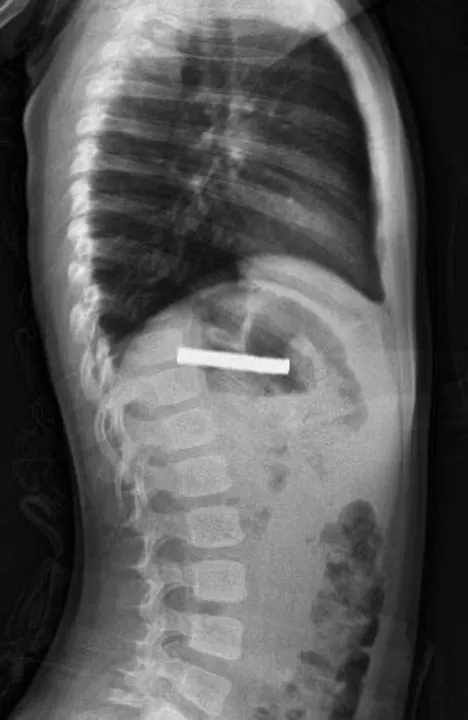

Çocuk, burada yapılan tetkiklerin ardından ambulans helikopterle Fırat Üniversitesi (FÜ) Hastanesi'ne sevk edildi. Hastanede, FÜ Çocuk Gastroenteroloji Hepatoloji ve Beslenme Bilim Dalı Başkanı Prof. Dr. Yaşar Doğan tarafından yapılan tetkiklerde mıknatısların yapışarak çocuğun yemek borusunu tıkadığı tespit edildi. Doğan ve ekibi tarafından yapılan müdahaleyle çocuğun yemek borusundaki mıknatıslar başarılı bir şekilde çıkarıldı. Bir süre gözetim altında tutulan çocuk daha sonra taburcu edildi.

Doğan, çocuğun durumunun acil olması nedeniyle ambulans helikopterle kendilerine getirildiğini belirtti. Yapılan operasyon hakkında bilgi veren Doğan, "Tabi bu mıknatıslar uzun süre hastanın yemek borusunda kaldığı için biraz hasar bırakmıştı. Çok güçlü mıknatıslardı. İşlemin kolay yapılabilmesi için mıknatıslar yemek borusundan mideye alındı, mideden özel bir fileyle çıkarıldı. İşlemden sonra hastayı gece boyunca gözlem altında tuttuk. Sabah da aile kendi isteğiyle çıkarmak isteyince, hastanın da genel durumu iyi olduğundan taburcu ettik." dedi.